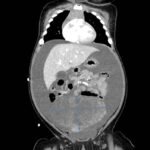

A 5-month-old female presented to the emergency department with worsening abdominal distention and postprandial emesis. Point-of-care ultrasound (POCUS) demonstrated extensive abdominal free fluid with a large, heterogeneous mass in the suprapubic region. This was confirmed on computed tomography (CT) of the abdomen and pelvis. The patient was urgently taken to the operating room for exploratory laparotomy where a ruptured tumor was discovered. The patient was eventually diagnosed with ovarian juvenile granulosa cell tumor. POCUS can be vital in guiding the recognition of rare pediatric conditions in the emergency department and should be considered in patients where there is concern for an acute abdomen.